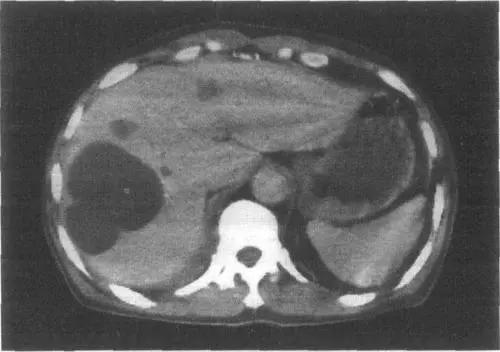

En général, si le kyste est petit et que le patient ne présente aucun symptôme, aucun traitement n'est nécessaire et un examen régulier suffit. Si un diagnostic clair a été posé, une échographie doit être réalisée tous les six mois environ afin d'observer tout changement dans le kyste.

Si le kyste mesure plus de 10 cm, une intervention chirurgicale est recommandée, généralement par laparoscopie, et l'opération est très traumatisante. Ces dernières années, certaines personnes ont commencé à pratiquer la thérapie interventionnelle, c'est-à-dire la ponction transhépatique percutanée sous guidage échographique, l'injection d'alcool anhydre après extraction du liquide kystique pour traiter les kystes hépatiques, mais pour les kystes hépatiques de grande taille, ils ne peuvent souvent pas être traités complètement en une seule fois, et doivent être injectés à plusieurs reprises.

L'examen de la fonction hépatique est généralement normal, l'examen échographique de la zone hépatique peut révéler plus d'un liquide de sécurité. La tomodensitométrie ou la scintigraphie nucléaire peuvent également vérifier la présence de kystes hépatiques multiples, en plus de déterminer que les kystes hépatiques multiples n'ont pas de lésions substantielles.